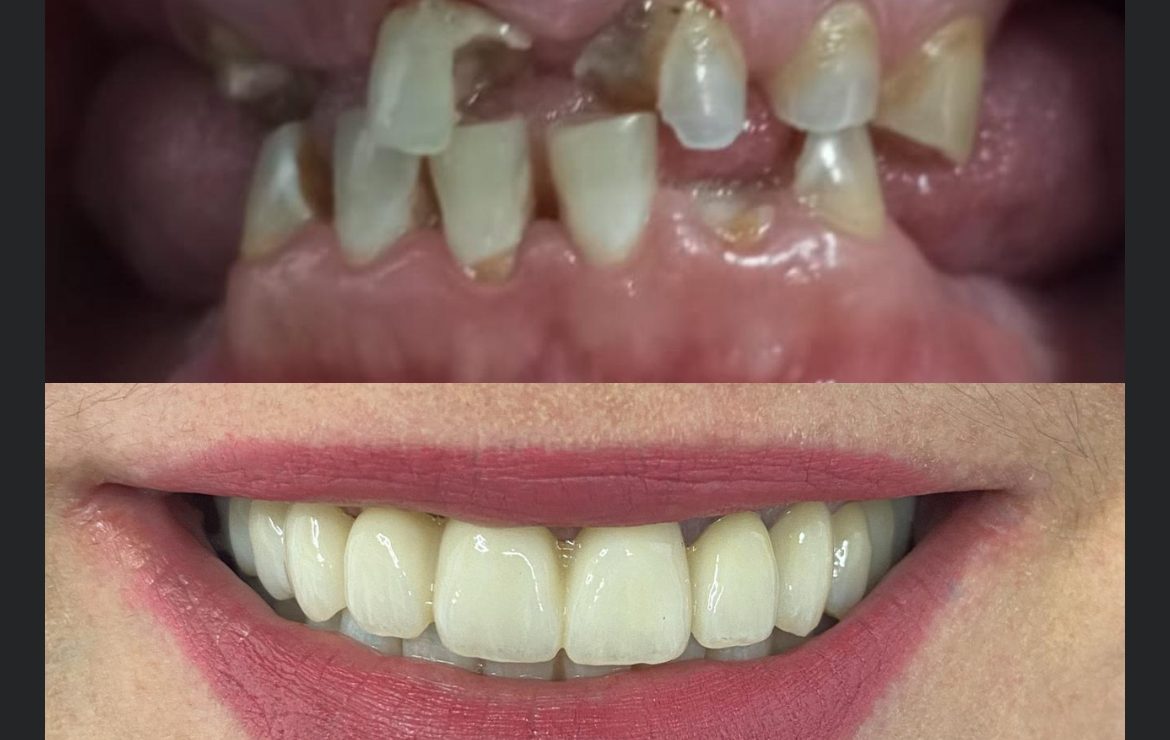

Caso Real: Rehabilitación Total con Prótesis de Carga Inmediata Superior e Inferior

Presentamos un caso de éxito en el que un paciente recibió una rehabilitación completa con prótesis de carga inmediata tanto en la arcada superior como en la inferior.

Antes del Tratamiento

El paciente presentaba pérdida dental severa y deterioro óseo, lo que afectaba su capacidad para masticar y su confianza al sonreír.

Después del Tratamiento

Tras la colocación de los implantes y las prótesis provisionales, el paciente recuperó la función completa y una sonrisa estética en solo 24 horas. Las radiografías muestran una integración adecuada de los implantes y una mejora significativa en la estructura ósea.